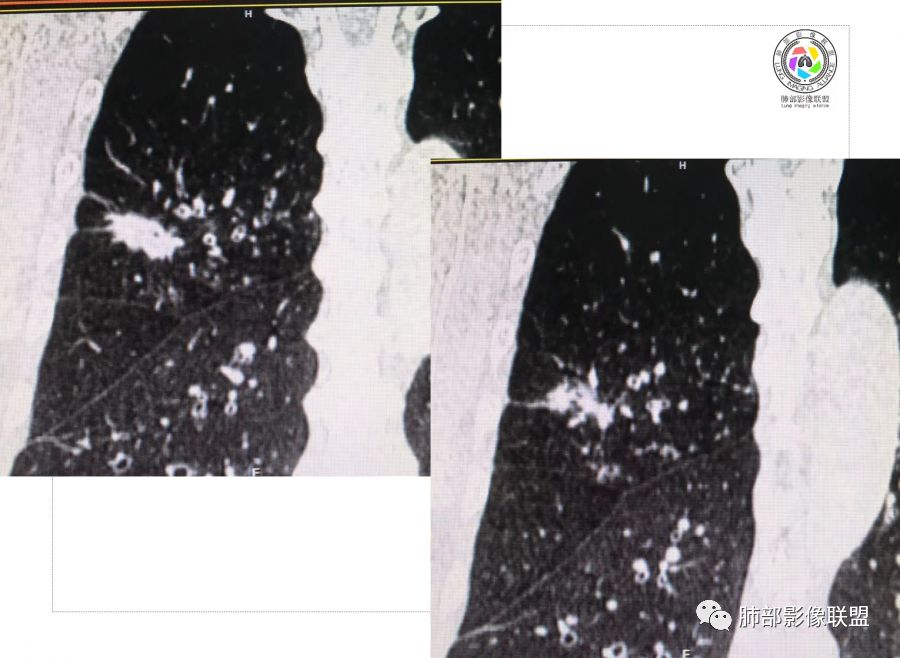

胸CT示病变位于右肺上叶,右肺上叶前段支气管壁不规则增厚狭窄、远端扩张。右肺上叶后段实变影,纵隔窗实变内可见钙化灶,可见支气管引流征,引流支气管壁明显增厚,边缘可见短硬毛刺,胸膜牵拉,u型征,周围可见卫星灶,并可见支气管扩张及其管壁增厚;病灶整体存在膨胀性生长。考虑良性病(结核)变基础上合并癌变,腺癌?

患者中老年男性,咳嗽喘息半年。查体双肺闻及哮鸣音。胸部CT:右肺上叶后段不规则结节灶,可见长毛刺、胸膜牵拉、分叶及钙化征象,周围见点片状卫星灶,近端支气管壁增厚,呈支气管爬行征。综合考虑结核。鉴别恶性病变。

右上肺的占位,毛刺,凹陷,总体偏恶性,但周围卫星灶,考虑腺癌可能性最大,结核也不能排除。

老年男性,咳嗽半年,右肺上叶后段实性结节伴粟粒状卫星灶,结节内有钙化,部分边缘平直,周围见长索条,有胸膜牵拉,结核是明确的,常规需要增强判断有无合并肺癌,当然该患者已经穿刺。

右肺上叶后段结节,点状钙化,边缘见细长毛刺,胸膜凹陷,卫星灶伴树芽症,支气管壁增厚扩张,有截断,考虑结核,但腺癌没法排除,确实有增强就基本能明确。

右肺上叶后段实性结节伴卫星灶,结节内有钙化,部分边缘平直,长索条,胸膜牵拉,考虑结核,但恶性征象还是有的,需除外腺癌!

右肺上叶后段不规则结节,长毛刺,卫星灶,斑点状钙化伴细小钙化,边缘部分平直,收缩力不强,倾向一元解释TB可能大,鉴别腺癌

右肺上叶病灶,可见分叶、毛刺、胸膜牵拉,周围见花花草草,似乎是卫星灶,考虑结核,鉴别腺癌。右肺支气管管壁增厚并扩张,考虑支扩,病史有喘息,哮鸣音,考虑合并有曲霉菌感染。综合考虑腺癌合并结核,曲霉感染。二元。

右肺上叶后段结节,长毛刺、钙化灶、近端小空洞、索条影、周围支气管树丫、引流支气管增厚,主体病灶侧后方分隔样空腔,弥漫支气管增厚,大气道受累,支持感染的征象较多,TB、曲霉;分叶、膨隆、脊状凸起、毛刺等恶性征象也有,遗憾没看到增强,只有期待活检一槌定音。

右肺上叶后段结节,呈不规则状,内可见钙化,边缘可见长短不一毛刺及胸膜牵拉,并可见分叶,邻近支气管管壁增厚,周围可见多发点状及结节状高密度影,首先考虑结核。

老年男性,咳嗽半年,右肺上叶后段实性结节,内见钙化,边缘部分膨隆,有长短毛刺、分叶、空泡征,胸膜侧见胸膜牵拉,周围不干净,见小卫星灶,右上叶后段支气管管壁增厚,扩张,有炎性及恶性征象,一元论常规考虑炎性肉芽肿病变,结核可能,腺癌不除外,二元结核并腺癌,建议增强及穿刺活检。

右上肺后段结节,边界清晰,可见分叶及毛刺,血管集束征,胸膜牵拉,内见斑点状钙化,周围见斑点状模糊影,同时伴支气管扩张,管壁增厚。整体感觉恶性征象多于良性,首先考虑肺癌,鉴别肉芽肿性病变,结核位置不像。

右肺上叶后段占位,毛刺,胸膜凹陷,病灶边缘内可见钙化、空泡,血管进入,病灶周围可见多发粟粒及树芽征,首先考虑肺结核;鉴别腺癌?鳞癌(周围小花、小草?)?

右上叶结节,毛刺、胸膜兔儿、空泡、钙化、血管,恶性征象不少,但是,可见沿支气管血管束分布的,周围可见卫星病灶,支气管扩张,外边胸膜是增厚的,结核可能性大。

中年男性,CT提示右肺上叶后段可见一结节影,可见长、短毛刺,胸膜牵拉,邻近支气管壁增厚,可见卫星灶,病灶内可见钙化,符合结核改变,腺癌待排。

右肺上叶后段团块影,内见钙化,周围胸膜有牵拉,近段支气管扩张管壁增厚,周围可见卫星灶,右支气管狭窄,综合考虑支气管内膜结核,鉴别真菌感染(气道侵袭性曲霉菌病)。

中老年男性,右肺上叶不规则团块状病灶,深分叶、长软毛刺,内部见空泡、多发钙化,相邻支气管增厚,考虑病变来源于气道,首先考虑结核,有空泡,这个腺癌多见,需要鉴别。

右肺上叶后段不规则结节,可见多发长毛刺,边界欠清,密度不均匀,其内可见斑点状钙化影,相应支气管壁增厚,管腔通畅,病灶周围见斑片状、斑点状稍高密度模糊影,考虑结核可能性较大。

中老年男性,右肺上叶不规则团块状病灶,深分叶、长毛刺,内部见空洞(近心侧)、钙化,相邻支气管增厚,有结核背景,首先考虑结核,腺癌需要鉴别。

右肺肿块,边缘平直,往下部分有膨胀感,毛刺、胸膜牵拉,内钙化,周围树芽,边界清,支气管壁增厚,考虑结核;不除外合并恶性。

右上后段结节,整体收缩,长软毛刺丶胸膜凹陷,有点状钙化丶小空洞,引流支气管明显管壁增厚,周边卫星灶明显,有喘息史半年,可能有应用激素史,致内源性复发,考虑TB,鉴别腺癌。

右肺上叶后段占位,分叶,毛刺,胸膜凹陷,病灶边缘内可见钙化、空泡,血管进入,病灶周围卫星灶,考虑肺结核合并肺癌。

不给增强图像,仅就形态判断,腺癌、结核都有可能。腺癌:分叶,毛刺,胸膜牵拉,近端支气管爬行结核:分叶,毛刺,胸膜牵拉,粗颗粒钙化散在分布,引流方向支气管壁增厚。这种情况通常放射科诊断不下结论:部位,病变,建议增强检查/穿刺活检。

这个病灶确实有点担忧局部边缘是膨隆的,结果腺癌,可能是结核合并了腺癌。

钙化与软组织成分明显不成比例时一定要小心ca,尤其钙化位于偏心的位置时,肿瘤包裹钙化。

南边:结核一定要下,癌肯定不能排除,不能排除的原因:粗短毛刺、膨隆。

3.本例病灶影像表现为:右肺上叶后段不规则结节灶,病灶整体存在膨胀性生长,可见毛刺、胸膜牵拉、分叶及钙化征象,近心端小空洞,周围见点片状卫星灶并出现磨玻璃影,近端支气管壁增厚,管腔扩张,既有恶性征象,也有结核的征象。南边老师考虑结核与腺癌同时存在,但遗憾的是缺乏增强扫描图像,亦未提供结核相关辅助检查结果。